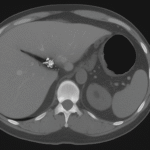

- Ultrasound:

The go-to investigation. Classic findings:- Gallstones

- Thickened gallbladder wall (>3 mm)

- Pericholecystic fluid

- “Sonographic Murphy’s sign” (pain when the probe touches the gallbladder)

CT is reserved for complications: gangrene, abscess, perforation.